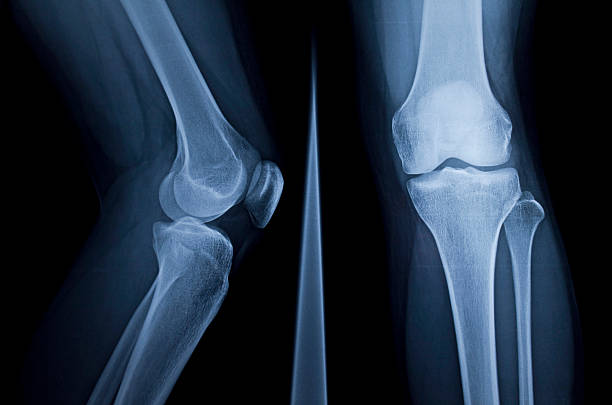

무릎연골은 대퇴골과 경골을 각각 3~4mm 두께로 감싸 관절에 가해지는 충격을 흡수하여 관절이 원활하게 움직일 수 있도록 하기 때문에 심한 충격이나 잘못된 자세로 계속 자극하면 연골이 닳거나 부러질 수 있어 일상 생활에서 관리가 필요할 수 있지만 연골에는 신경이 없어 찢어지거나 닳아도 아프지 않아 연골이 마모되더라도 연골이 아픈 것이 아니라 아래의 뼈가 노출되어 통증을 유발하기 때문에 연골이 손상되었다면 스스로 치유되거나 재생되지 않는다는 점이기 때문에 미리미리 원인을 알고 대비해야합니다.

무릎 연골 손상 증상은 이미 연골이 찢어지고 부러진 경우 통증이 너무 크기 때문에 무릎을 구부리거나 펴거나 제대로 기능하지 못하는 경우가 돼서야 인식하는 경우가 많습니다. 이 경우 연골에 염증이 생기고 증상이 너무 심해 병원에 가서 진찰을 받아야하며 정확한 검사 없이는 정확한 진단이 불가능하고 적절한 치료를 받을 수 없기 때문에 준비를 잘 하셔야 합니다.

무릎 연골 손상은 무릎 관절을 사용하여 움직일 때도 통증을 유발할 수 있습니다. 통증은 무릎 연골의 파열로 인해 발생하는 가장 흔한 통증으로 걷거나 계단을 내려갈 때 또는 내리막길에서 통증을 경험할 수 있어 빠른 치료가 요구됩니다.